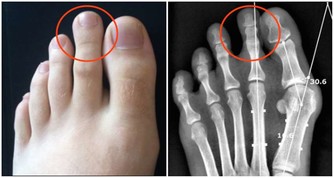

01.腿腳要求減負擔

腿腳是骨骼、肌肉、關節形成的“鐵三角”,幾乎承載著身體的整個重量,僅膝蓋就承受9倍於體重的壓力。

腿腳還是交通樞紐,佈滿了人體50%的神經、50%的血管,流淌著50%的血液。

負擔過重、行動姿勢不當、寒氣侵入等都會讓腿腳受傷。另外,腿腳最容易受到傷害的地方是關節。